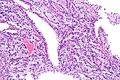

Prostatic-type polyp. H&E stain. (WC/Nephron) | |

| LM | benign prostatic type epithelium or transitional type epithelium +/-corpora amylacea |

| LM DDx | prostatic ductal carcinoma |

| IHC | PSA +ve |

| Site | urethra/prostate gland - verumontanum |

Prostatic-type polyp is an uncommon polyp of the genitourinary tract. It is typically centered on the verumontanum of the prostate gland and projects into the urethra.

Features:[2]

- Benign prostatic type epithelium or transitional type epithelium.

- Cuboidal to low columnar cells with basal cell layer.

- +/-Corpora amylacea.